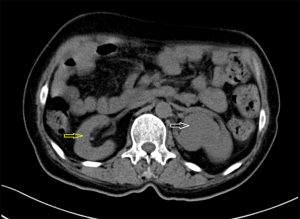

A 45-year-old woman was admitted to hospital complaining of a 1-month history of dizziness, and a transient ischemic attack was diagnosed. During a lung examination, her left kidney was found to be abnormal. The patient was not known to have kidney abnormalities, and there was no genetic history of this condition in her family. The patient did not present clinical symptoms of low back pain, hematuria, or urinary tract infection, and laboratory tests of renal function and urine routine were within normal ranges. The patient had no history of hypertension. A CT plain scan showed abnormalities in the left renal artery, vein, and ureter, and a reversed renal parenchyma with the collecting system protruding, while the right kidney was completely normal. Enhanced CT suggested that there was an artery in the left kidney, which entered the renal parenchyma in a mesh shape. There were 2 primary thick branches of deep veins, which merged with the reproductive vein at the renal pedicle and then merged into the inferior vena cava. The renal parenchyma was in a state of eversion and folding, and the renal papilla was prominent. Each renal papilla corresponded to a renal calyx, which converged into the renal pelvis on the ventral side (Figures 1,2). Using a software application (Mimics Innovation Suite 19.0, Materialise, Leuven, Belgium), we created a 3D reconstruction of the patient’s kidneys. The 3D-reconstructed images (Figures 3,4) showed that the right kidney was normal in anatomy and that the left kidney was abnormal. In Figures 3,4, it can be seen more intuitively and clearly that the left kidney has poor rotation, irregular physical contours, and an uneven surface; the renal pelvis and ureter are distributed in a “Y” shape. The final clinical diagnosis was CAKUT, and the patient’s clinical symptoms disappeared after conservative treatment. As the patient had no urinary system discomfort and her physical and laboratory examinations were normal, we prescribed a dynamic observation treatment plan with annual renal function and urinary system USs.